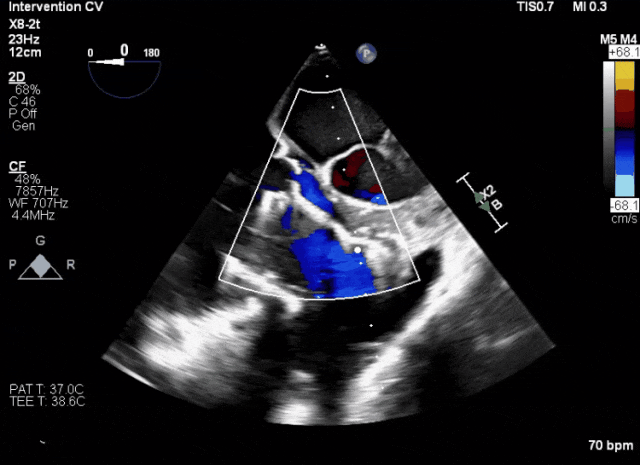

術中TEE成像困難,偽影干擾

術后DSA、超聲顯示人工瓣膜穩定性良好,瓣葉啟閉正常,無瓣周漏